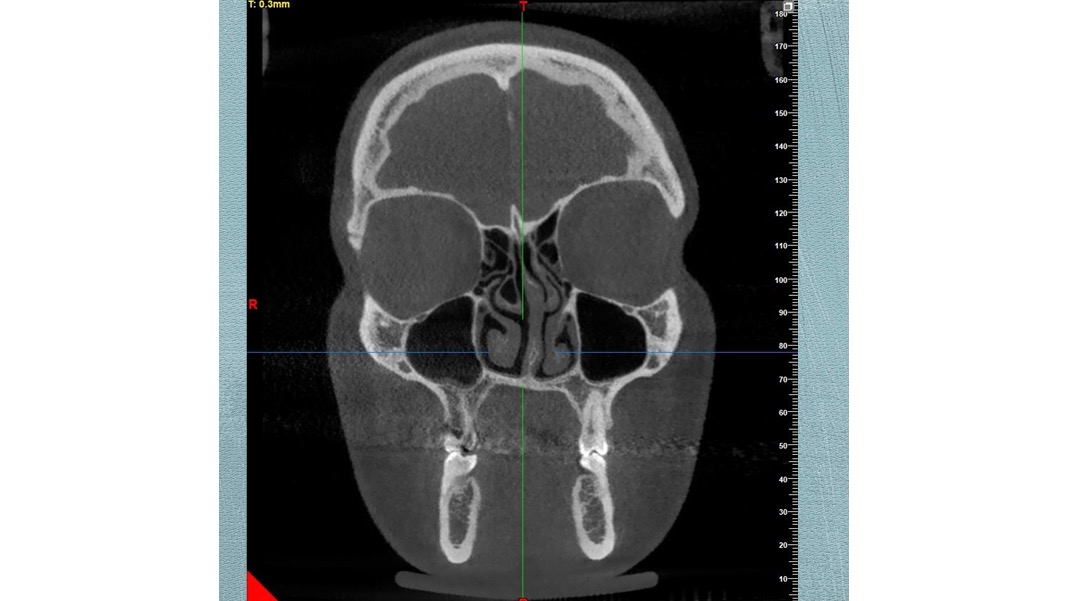

I had a dental procedure take place in 2019, which has cost me 4 years of my life living in chronic pain, misplaced jaw, breathing issues, fatigue and basically bed ridden terms. After many treatments that haven’t helped, many referrals to medical professionals, I am now booked in to have Double Jaw Surgery in July 2024 to fix my misaligned jaw, my uneven non existent bite, my headaches, neck issues as well as most importantly my breathing / airways.

I had a dental procedure take place in 2019, which has cost me 4 years of my life living in chronic pain, misplaced jaw, breathing issues, fatigue and basically bed ridden terms. After many treatments that haven’t helped, many referrals to medical professionals, I am now booked in to have Double Jaw Surgery in July 2024 to fix my misaligned jaw, my uneven non existent bite, my headaches, neck issues as well as most importantly my breathing / airways.